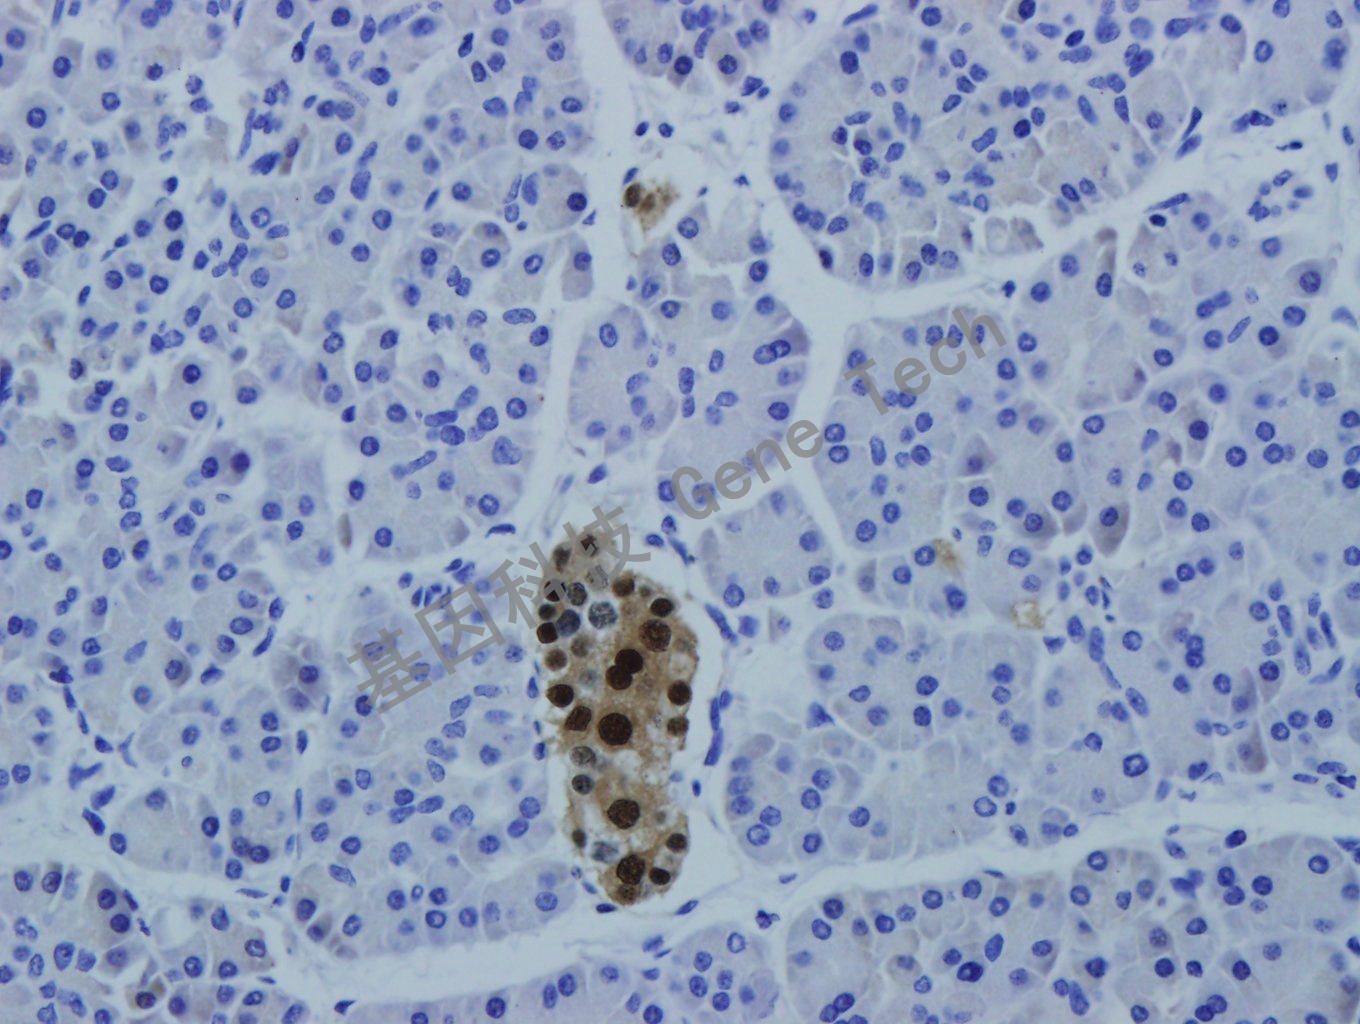

| 預(yù)處理:高pH熱修復(fù) | 陽性部位:細(xì)胞核 | 陽性對照:胰腺癌 |

| 胰腺石蠟切片,用 PAX-6(GT2278)染色,細(xì)胞核陽性,DAB 顯色。 | ||